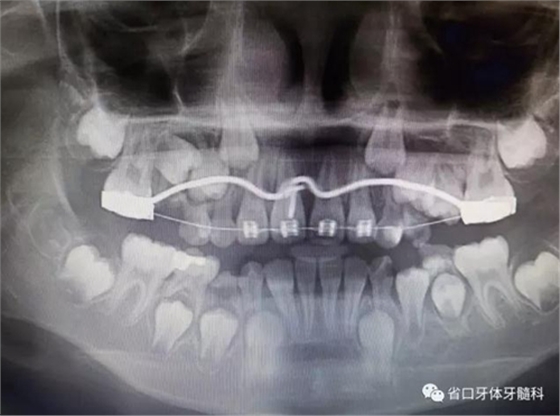

X線檢查:全景片

CBCT顯示右上中切牙埋伏阻生,牙軸呈水平位,冠向唇側(cè)、

根向腭側(cè),與鄰牙成90°夾角,牙根尚未發(fā)育完成,根端輕微彎曲。

全景片顯示11牙根發(fā)育良好